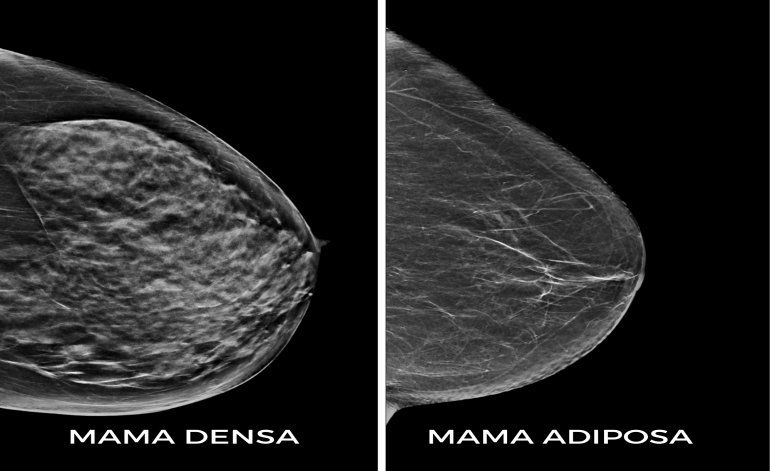

Con respecto a qué tipo de mamas requieren otros estudios, la médica explicó: “Las mujeres que en la mamografía tienen alta densidad mamográfica o “mamas densas” como se expresa popularmente (se ven más blancas que grises), también corresponden al grupo de riesgo intermedio.

Estas mamas presentan mayor dificultad para encontrar carcinomas (que al igual que la glándula mamaria normal son blancos en la mamografía) y por lo tanto pueden quedar ocultos. La alta densidad mamaria también representa mayor riesgo de desarrollar un cáncer de mama respecto de la mama mayormente compuesta por tejido graso (entre 4 y 6 veces)”.

“Por tal razón, es recomendable que quienes tengan mamas densas, las cuales son informadas en la mamografía como heterogéneamente densas o extremadamente densas, completen su estudio con ecografía mamaria o resonancia con contraste, si tienen otros factores de riesgo asociados”.